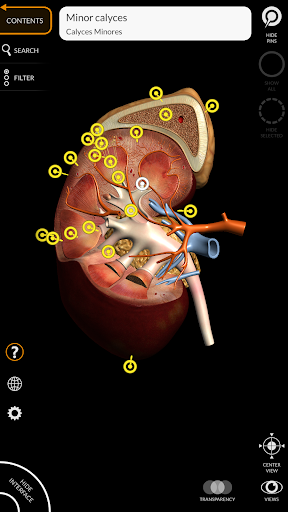

"Anatomía - Atlas 3D" permite estudiar la anatomía humana de forma fácil e interactiva.

A través de una interfaz sencilla e intuitiva es posible observar cada estructura anatómica desde cualquier ángulo.

Los modelos anatómicos 3D son especialmente detallados y con texturas de hasta una resolución de 4k.

La subdivisión por regiones y las vistas predefinidas facilitan la observación y el estudio de partes individuales o grupos de sistemas y las relaciones entre los diferentes órganos.

nervioso • Sistema respiratorio • Sistema digestivo • Sistema urogenital (masculino y femenino) • Sistema endocrino • Sistema linfático • Sistema ocular y auditivo CARACTERÍSTICAS • Interfaz sencilla e intuitiva • Rotar y hacer zoom en cada modelo en el espacio 3D • Opción para ocultar o aislar uno o varios modelos seleccionados • Filtro para ocultar o mostrar cada sistema • Función de búsqueda para encontrar fácilmente cada parte anatómica • Función de marcador para guardar vistas personalizadas • Rotación inteligente que mueve el centro de rotación automáticamente • Función de transparencia • Visualización de músculos a través de niveles de capas desde las superficiales hasta las más profundas • Al seleccionar un modelo o un pin, aparece el término anatómico relacionado • Descripción de los músculos: origen, inserción, inervación y acción • Mostrar/ocultar interfaz de usuario (muy útil con pantallas pequeñas) MULTILINGÜE • Los términos anatómicos y la interfaz de usuario están disponibles en 11 idiomas: latín, inglés, francés, alemán, italiano, portugués, turco, ruso, español, Chino, japonés y coreano • Los términos anatómicos se pueden mostrar en dos idiomas simultáneamente REQUISITOS DEL SISTEMA • Android 8.0 o posterior, dispositivos con al menos 3 GB de RAM Reversi